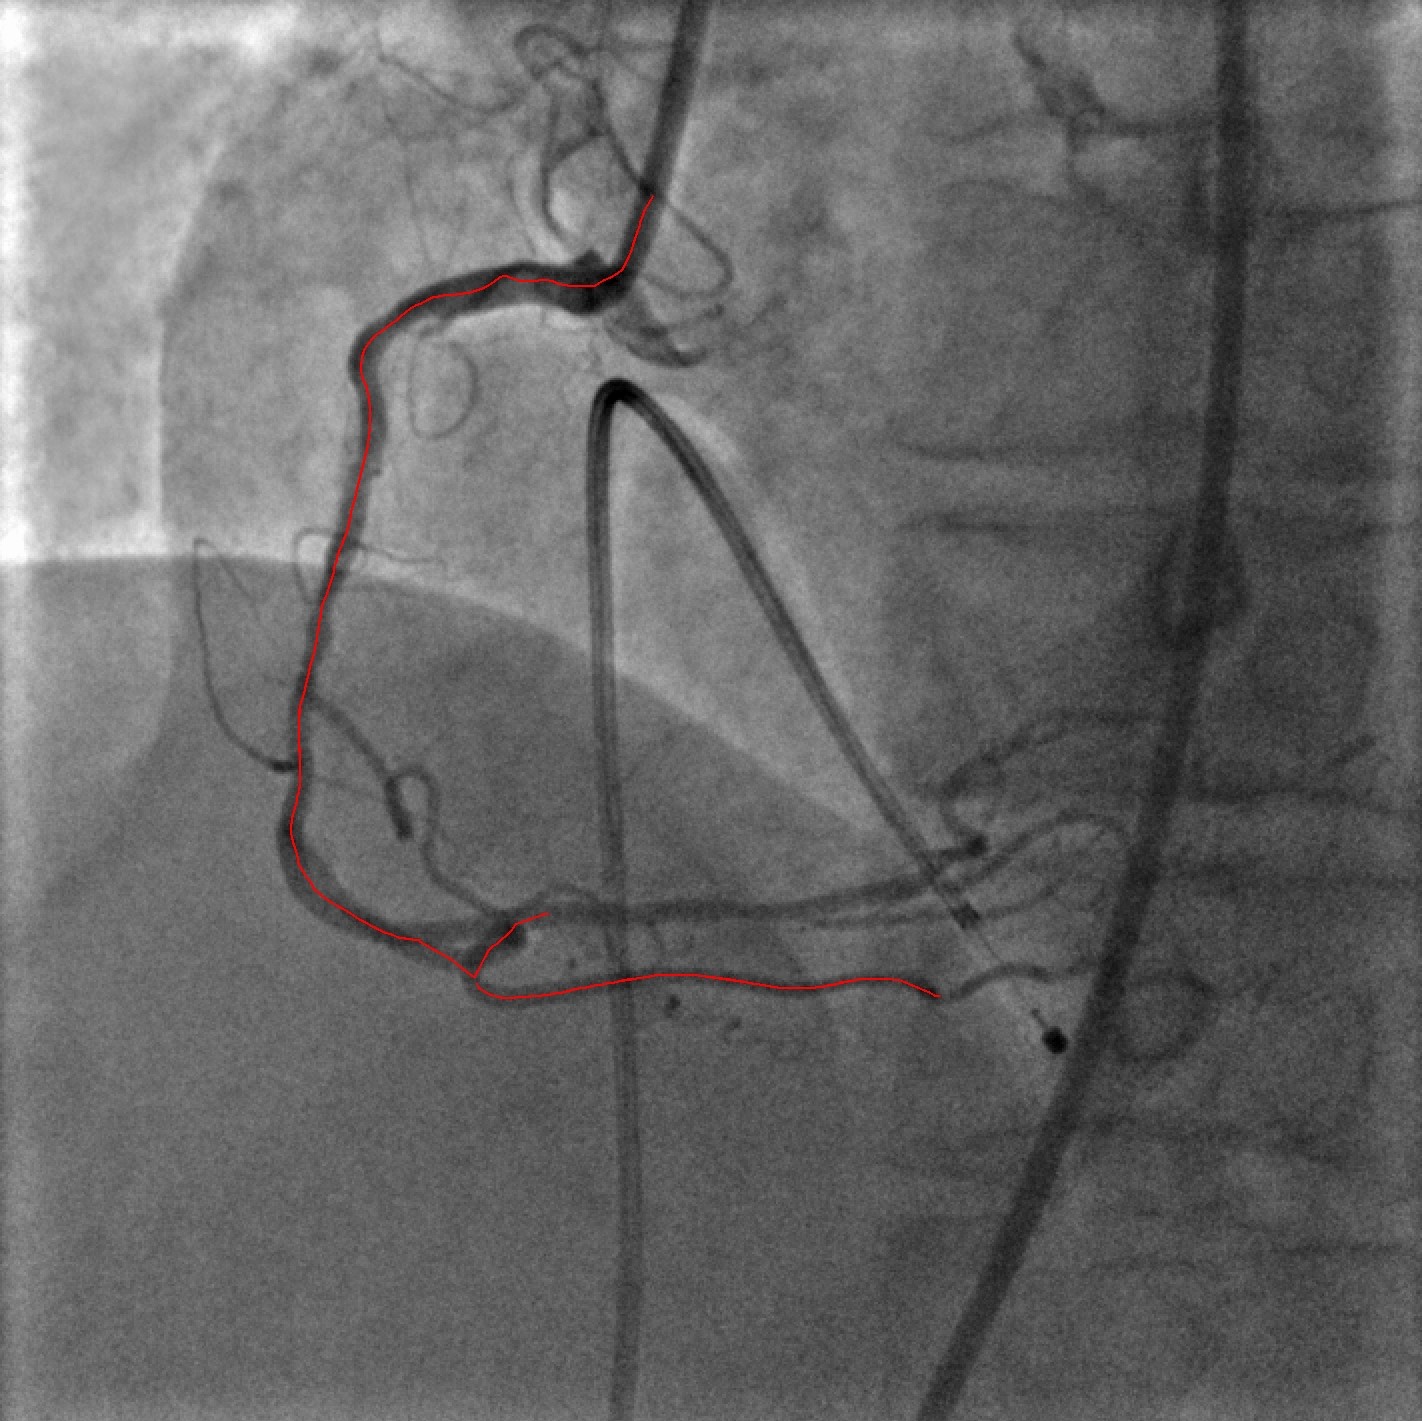

Refer to captionRefer to captionRefer to captionRefer to captionRefer to captionRefer to captionRefer to captionRefer to caption

Figure 1: VOIDD: (from left to right)Input image f𝑓f; centerline of segmented guidewire tip; tip candidate (red) matched to vessel centerline (green) marked by pairings(blue); corresponding location (green) of guidewire tip(red) inside vessel.

In the work presented here, we develop methods based on image processing to combine the information from fluoroscopic image sequences acquired at different steps of the procedure. More precisely, we consider two types of images: i) the images from reference sequence, which are injected with contrast agent to depict the vasculature and ii) the images from navigation sequence, which are acquired during the navigation of the tool and especially the guide wire, which is navigated from the ostia of the coronary artery down to the distal part after crossing the lesion. The imaging of the vessel with contrast agent provides information on the potential location of the stenosis. The ECG of the patient is recorded along with the images. Standard algorithm as [4] can then be used to identify the subset of the images where the coronary images are well opacified with the contrast agent. In this subset, a reference sequence of about 10 to 15 images is then selected that covers a full cardiac cycle and includes best opacified images. The navigation sequence is obtained with a low dose acquisition mode called fluoroscopy. The guidewire, a very thin (wire-like) object of diameter 0.014′′superscript0.014′′0.014^{\prime\prime} has two sections. The distal section, called as the tip, is more important and is enough radio opaque to be seen with low dose X-ray mode. Our aim is to automatically identify navigation sequence and determine the vessel-of-intervention which is going to be treated in the following steps of the PCI procedure, such as lesion reparation with angioplasty balloon, stenting, post-dilatation.